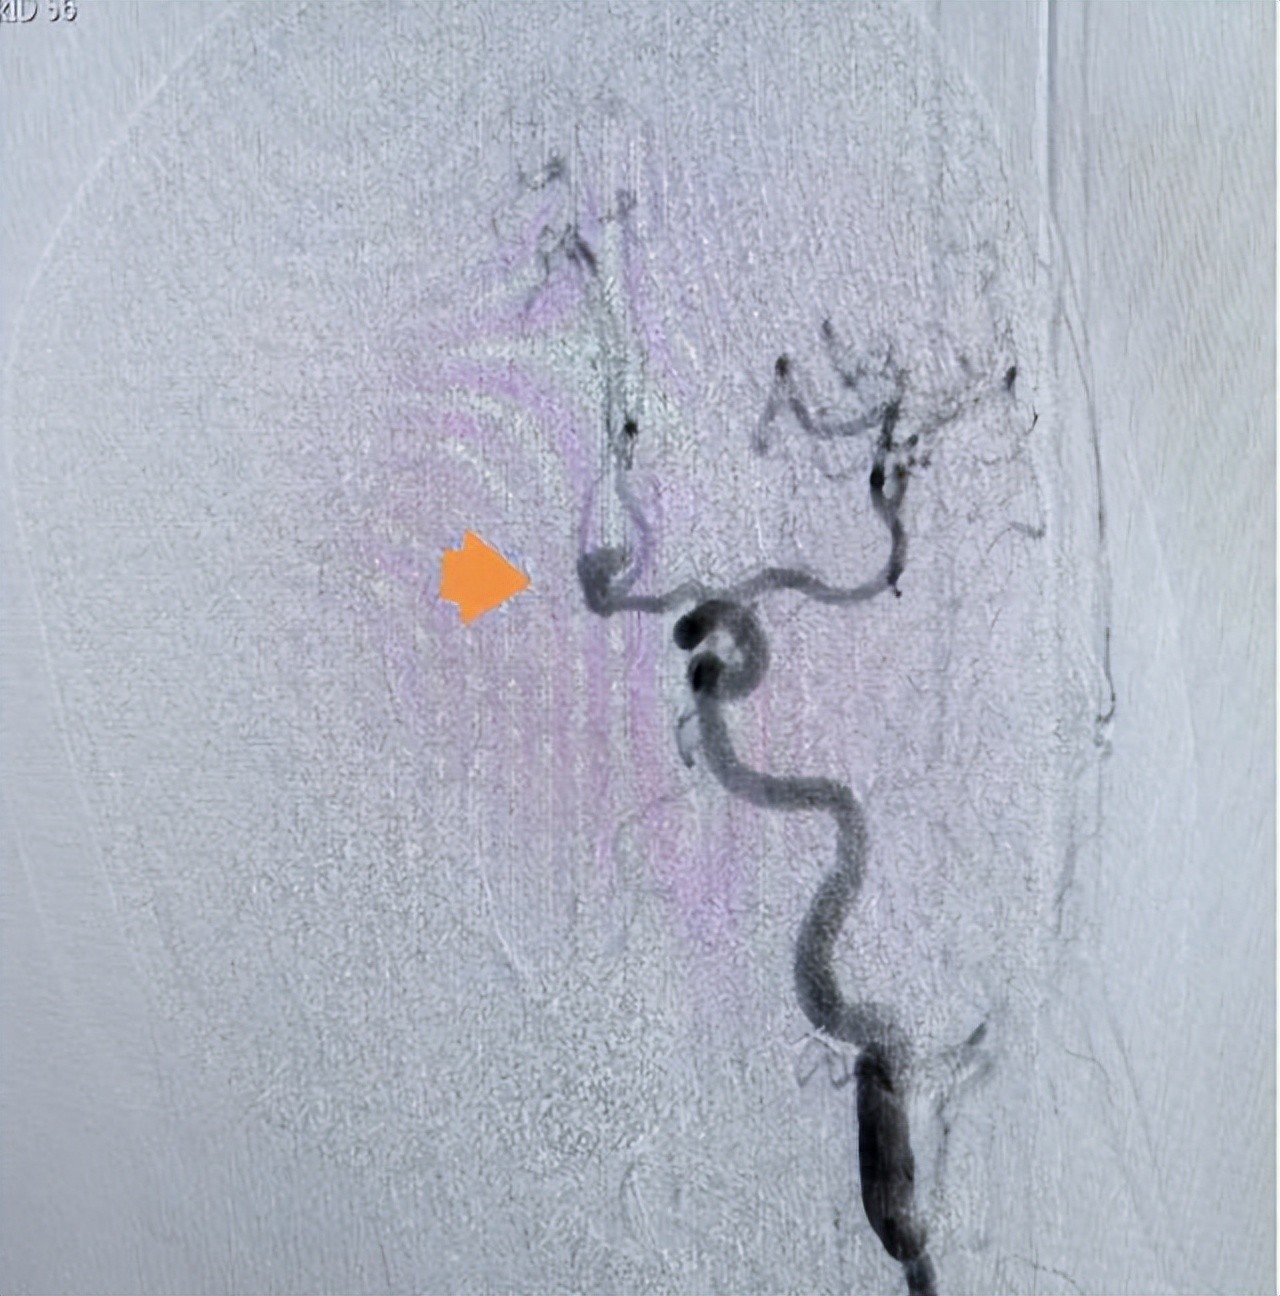

术前影像

时间就是生命!安居区人民医院卒中中心绿色通道立即启动,迅速安排头颈部CTA检查,很快锁定“罪魁祸首”——前交通动脉瘤!患者随即被收入ICU,但病情急转直下:呼吸困难、意识模糊……极有可能是动脉瘤再次破裂出血!若不立即手术,随时可能失去生命!与家属紧急沟通后,一场惊心动魄的“拆弹”手术即刻展开!

术中造影显示,刘女士的动脉瘤直径达8.5mm×7.0mm,形态复杂,尖端呈血泡样,这是动脉瘤中最凶险的类型之一,随时可能再次破裂!凭借精湛的技术和丰富的经验,专家团队沉着应对,成功实施“支架辅助弹簧圈动脉瘤栓塞术”,将这颗“炸弹”彻底“拆除”!